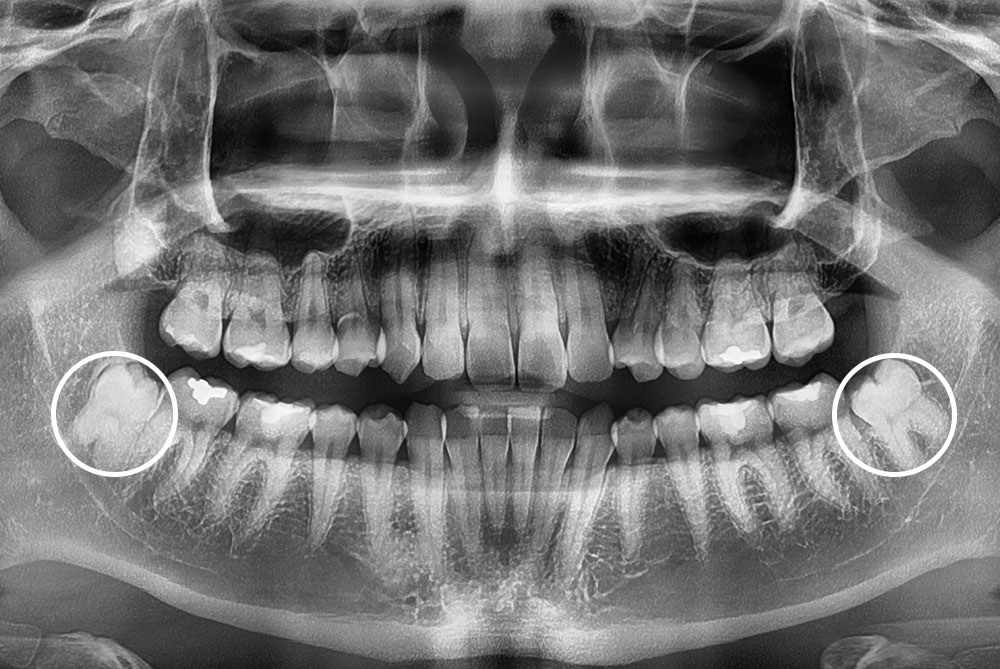

[사랑니] 매복 사랑니 발치

치료전 : 2022-07-18